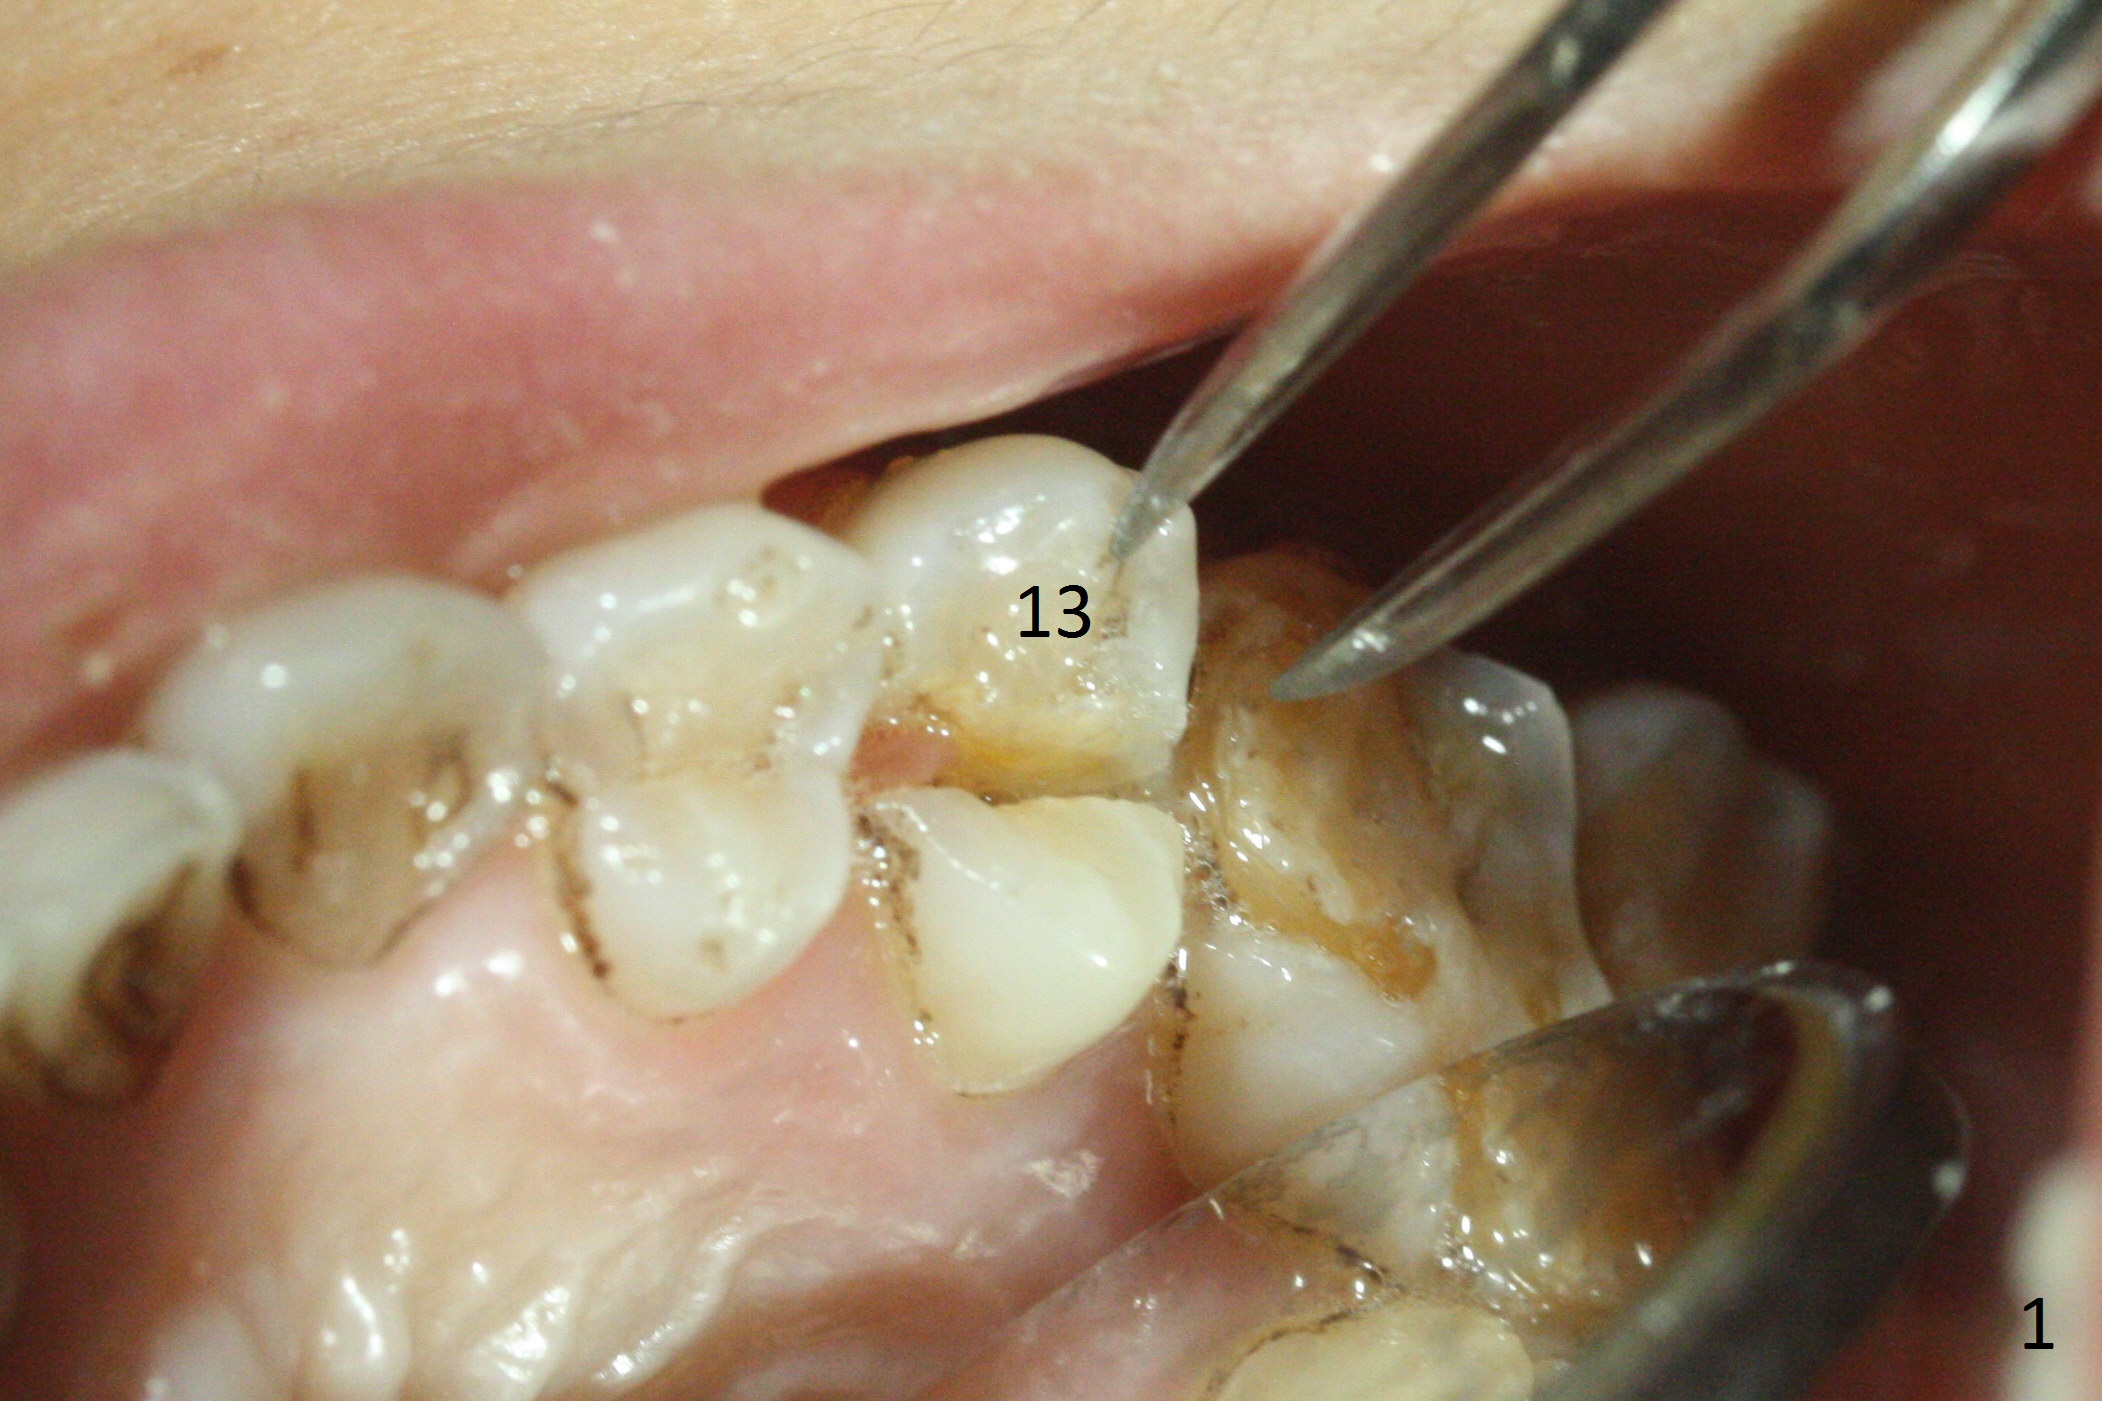

A 42-year-old woman presents to clinic with cc "top left tooth cracks upon biting on a small piece of stone". The buccal gingiva is tender, corresponding to the loose buccal segment of the tooth #13 (Fig.1). The crack may be secondary to severe wear of the 1st molar (Fig.1,2) in addition to deep slope of the affected tooth. A 4.5x15 mm IBS implant will be placed (Fig.3). Take PA following pilot drilling.